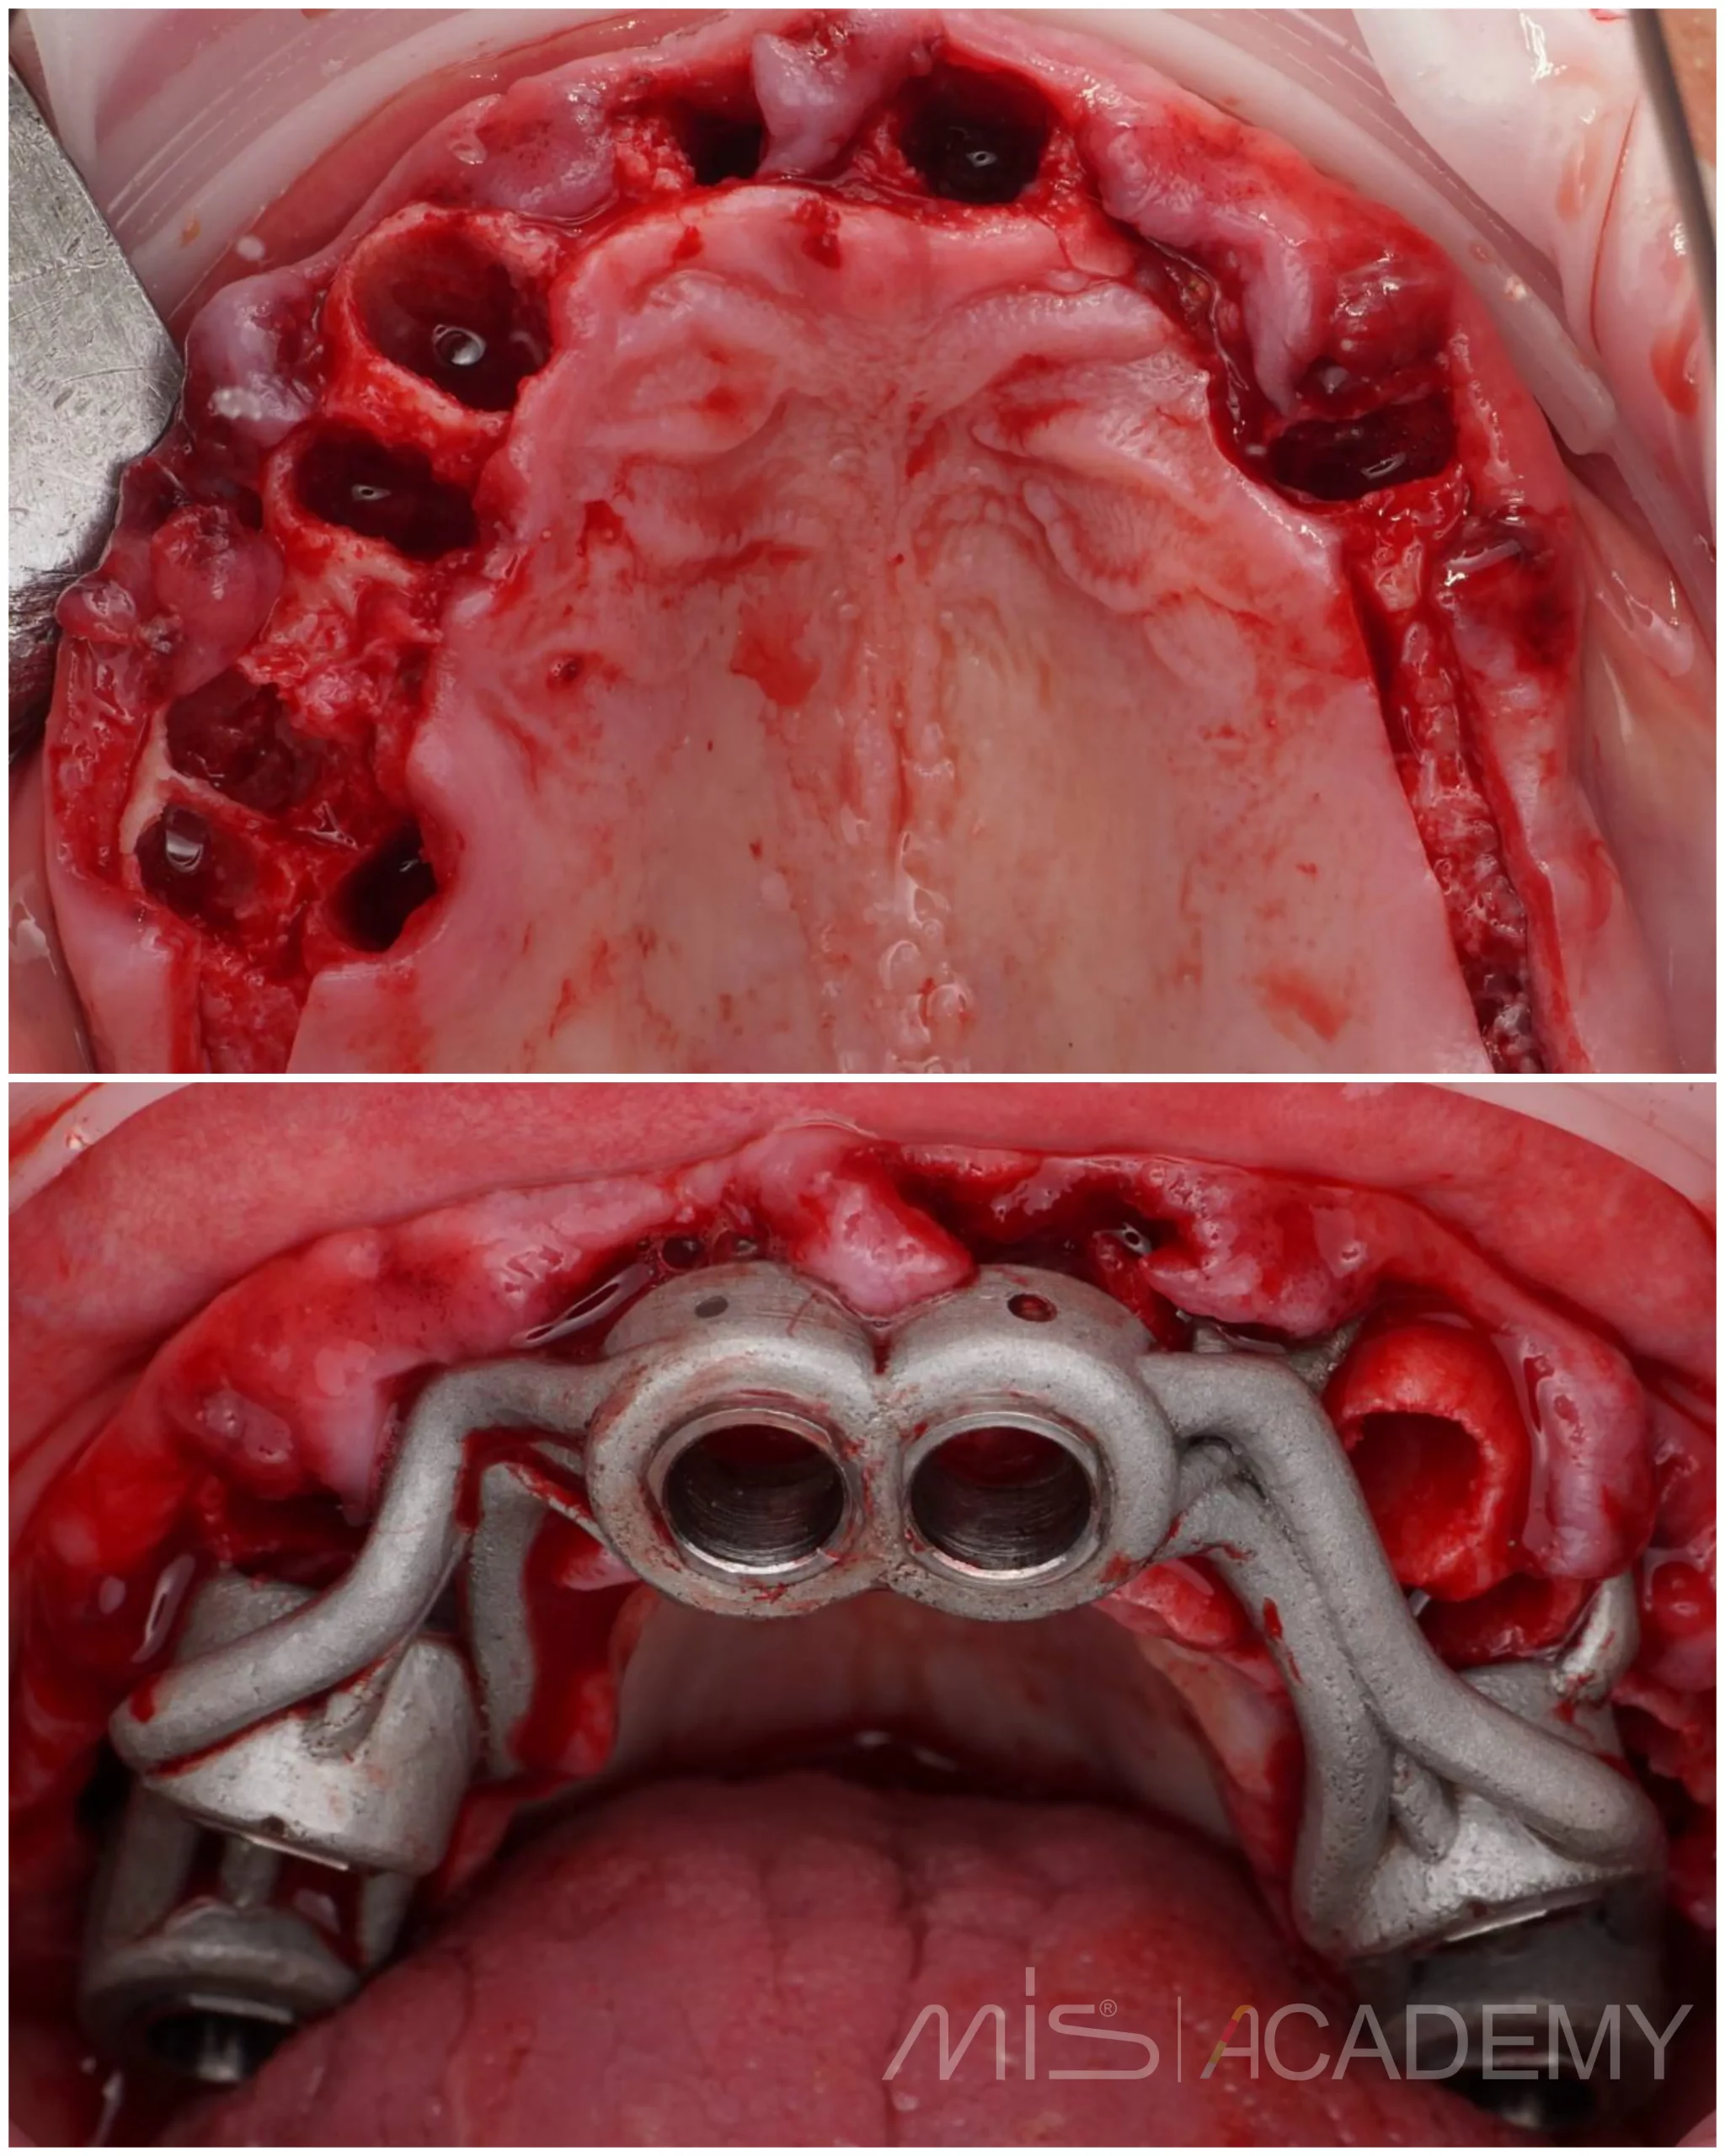

— Удаление всех несостоятельных зубов на верхней челюсти.

— Установлены имплантаты Mis C1 и два открытых синус лифтинга в дистальных отделах.

— Коннект абатменты и угловые МЮ.

— Проведено B2S в области дефекта костной ткани 1.1.

— Мягкотканная пластика.

— Балка, сварка, временный протез.